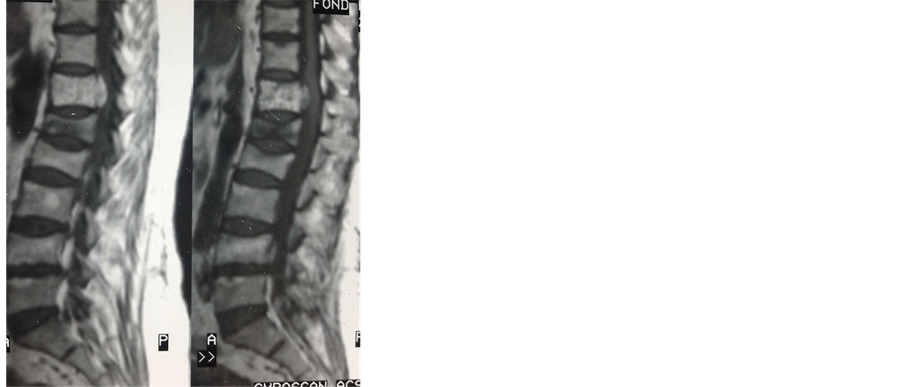

Plain radiographs of the thoracolumbar spine showed L1 and L2 benign vertebral fractures with grid appear- ance at T12 vertebra (Figure 1). MRI revealed T12 intensity signal on T1 and T2 with ductal extension, com- patible with aggressive vertebral angioma (Figure 2 and Figure 3).

Figure 2. Sagittal thoraco-lumbar spine MRI showed intensity T12 signal T1 and T2, with spine canal extension and L1 benign vertebral fractures.